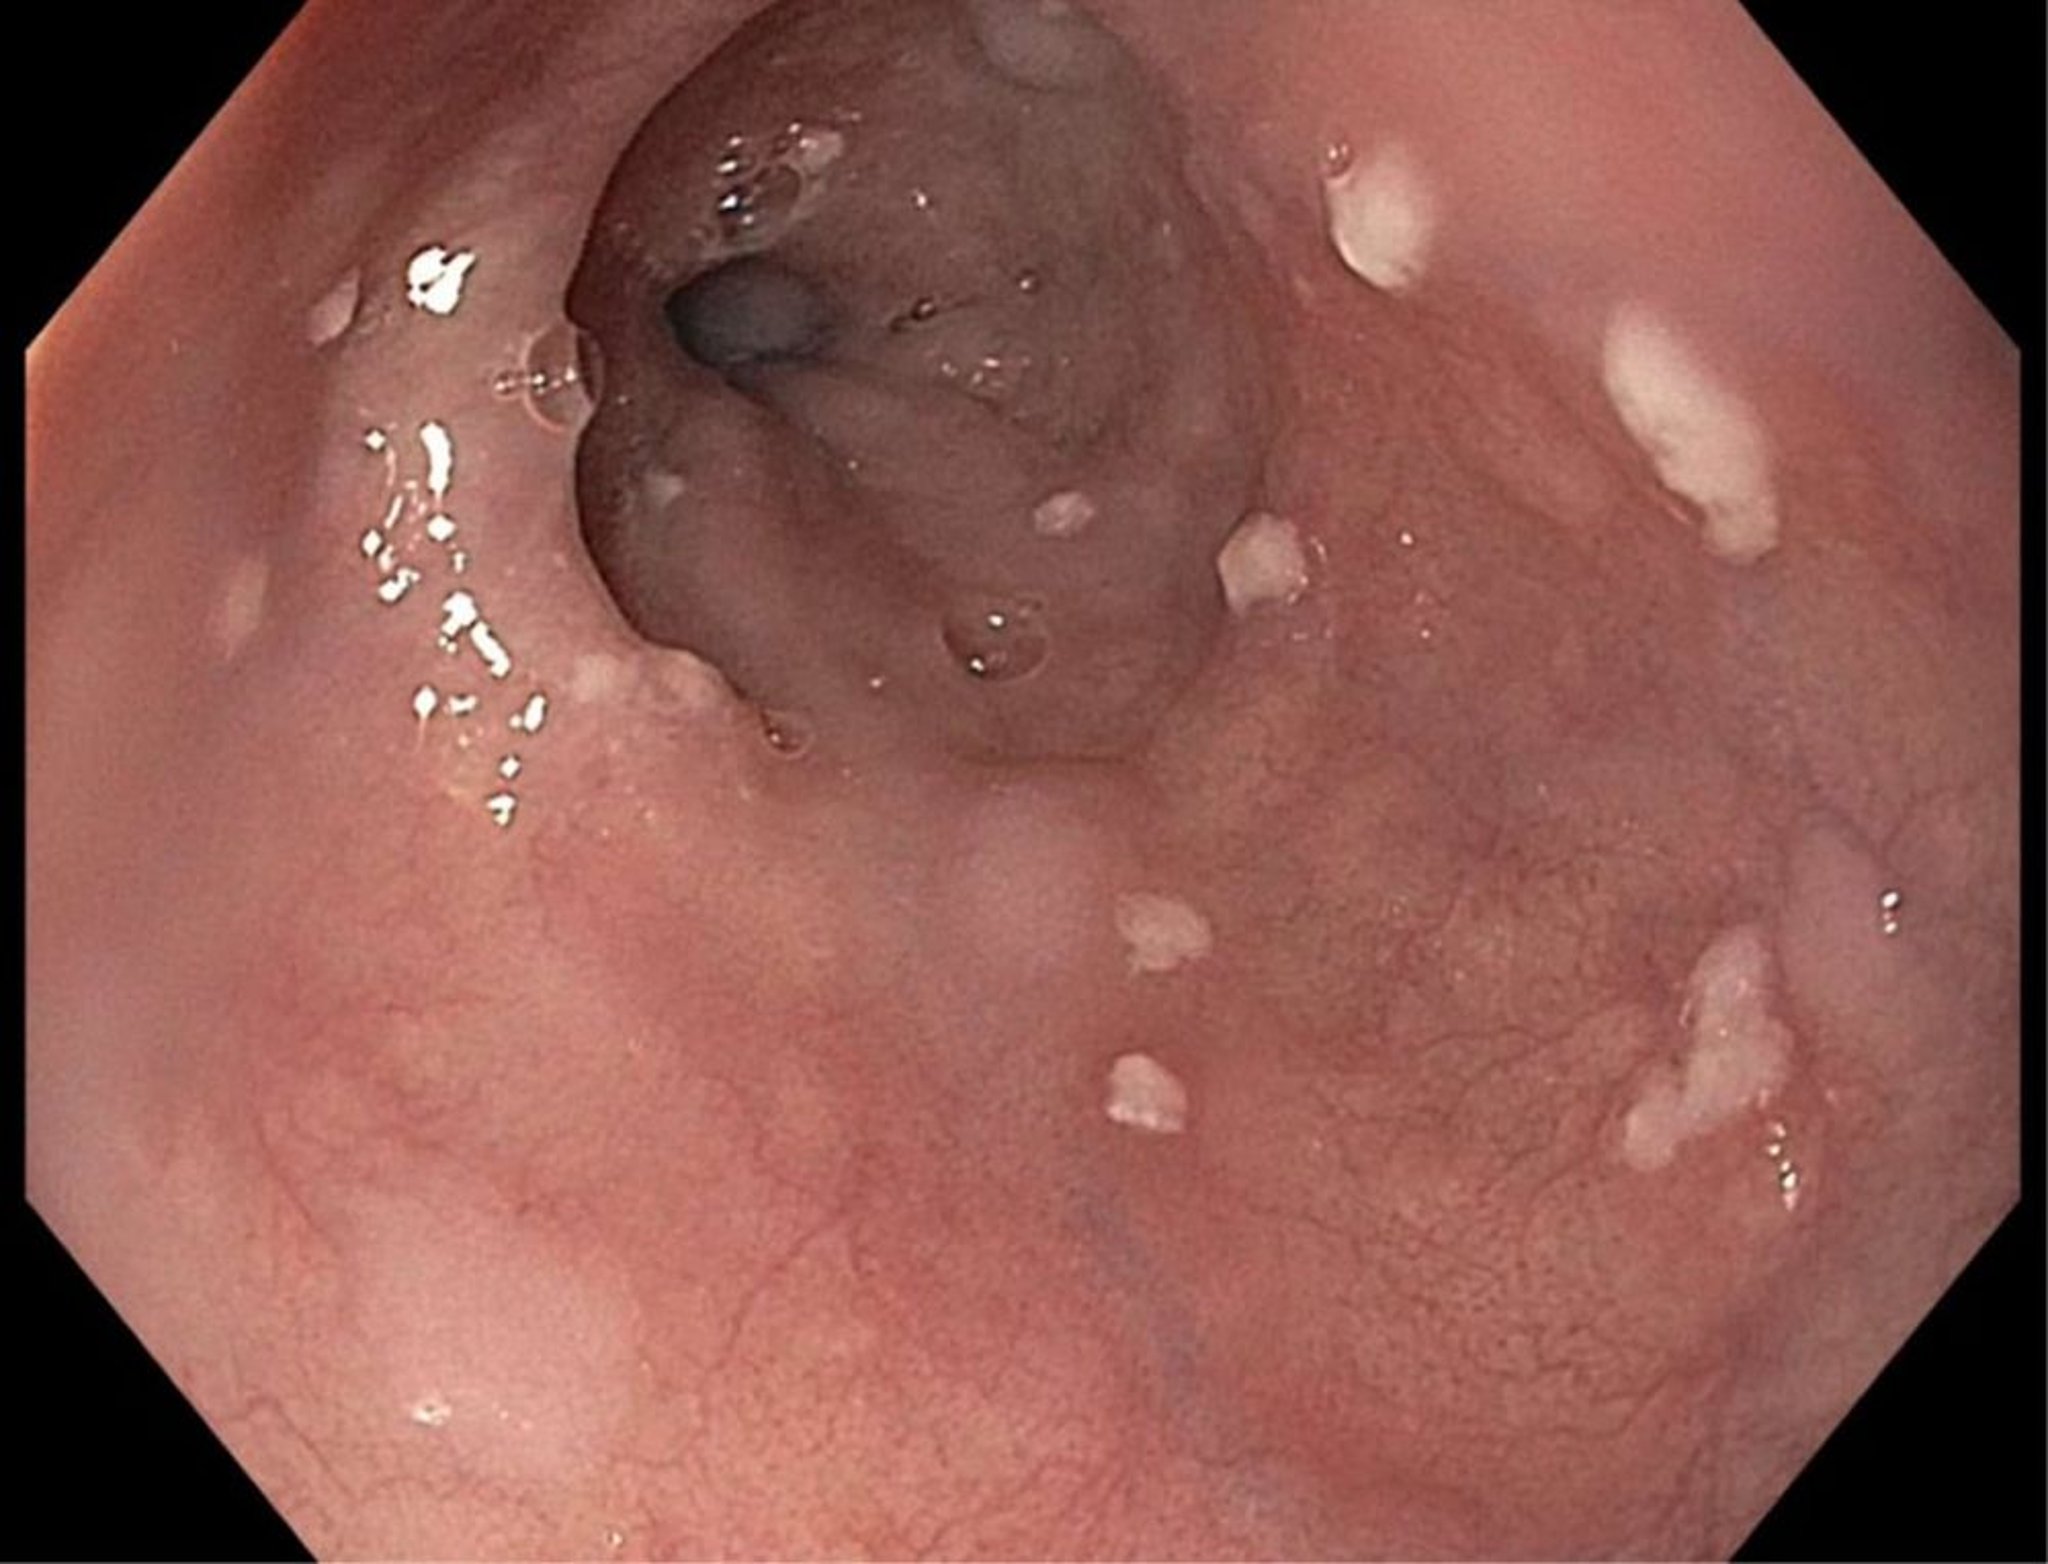

Candida-Ösophagitis

Patienten mit einer Candida-Ösophagitis leiden im Allgemeinen unter Odynophagie und weniger häufig unter Dysphagie.

Ungefähr zwei Drittel haben Zeichen eines Mundsoors, obwohl sein Fehlen eine Beteiligung des Ösophagus nicht ausschließt. Patienten mit Odynophagie und typischem Soor können empirisch behandelt werden, wenn allerdings nach 5–7 Tagen Behandlung kein wesentlicher Erfolg eintritt, muss eine endoskopische Untersuchung durchgeführt werden. Der Bariumbreischluck ist weniger genau.

Image provided by Kristle Lynch, MD.

Die Behandlung einer Candida-Ösophagitis erfolgt mit Fluconazol 200–400 mg p.o. oder IV einmal täglich für 14–21 Tage (1). Alternativen sind andere Azole (z. B. Itraconazol, Voriconazol, Posaconazol) oder Echinocandine (z. B. Caspofungin, Micafungin, Anidulafungin). Eine topische Therapie spielt keine Rolle.